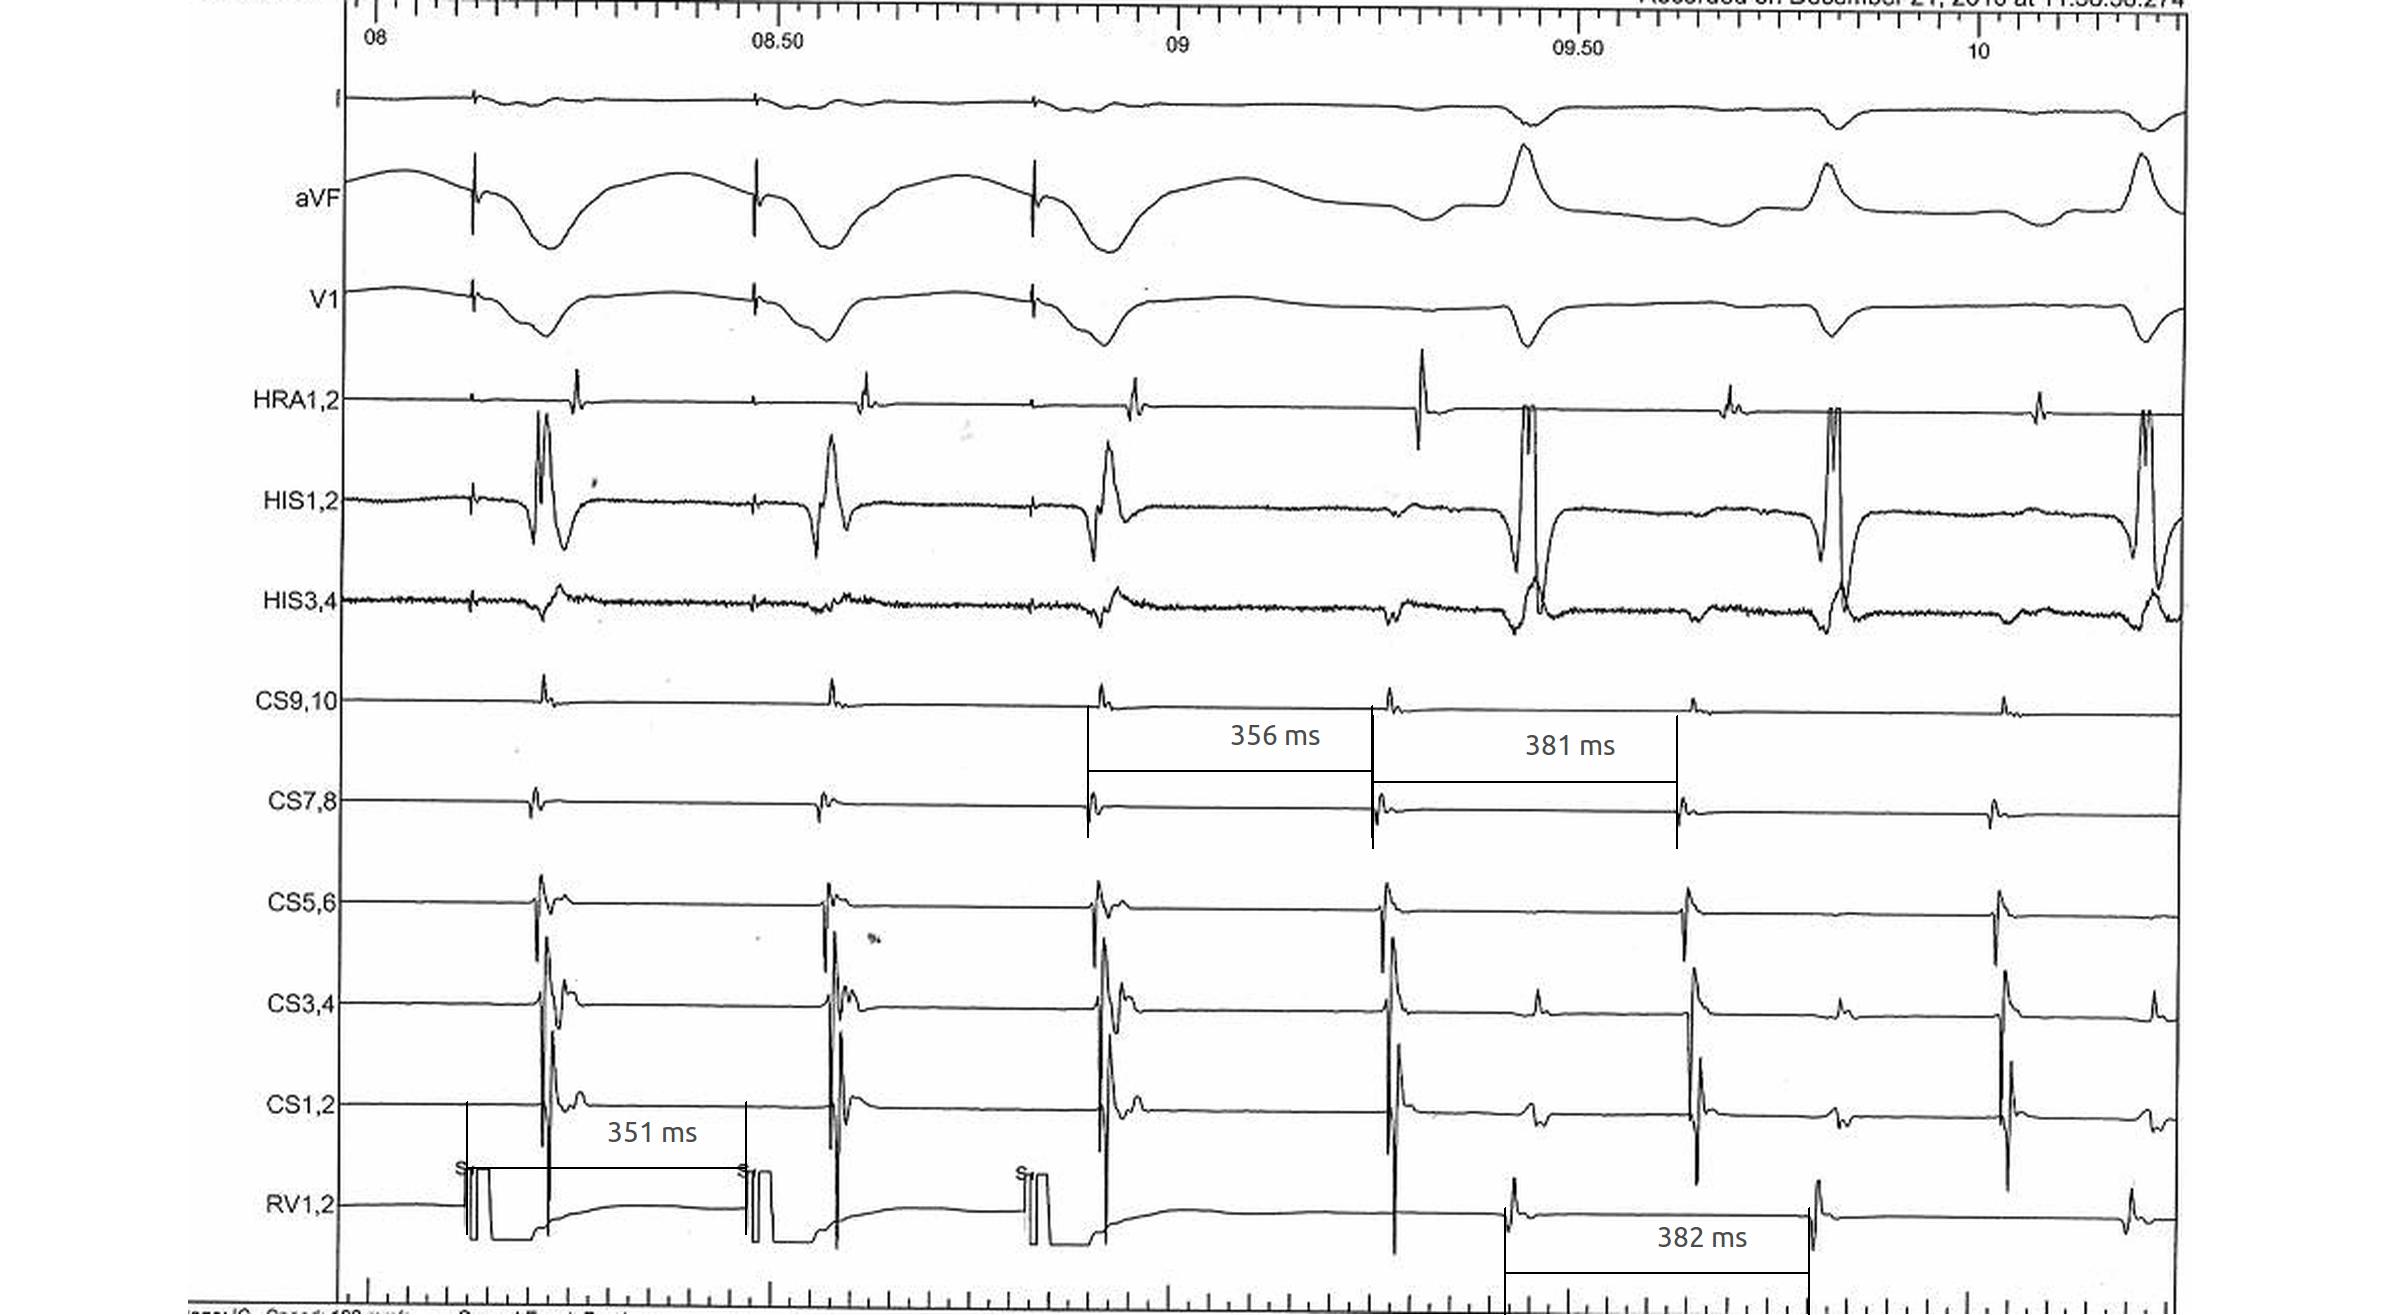

Differential pacing

• VA interval during pacing from apex and base

• Shorter from apex for nodal conduction

• Shorter from base for AP conduction

RV apex pacing

rv_apex_va.jpg

RV base pacing

rv_base_va.jpg